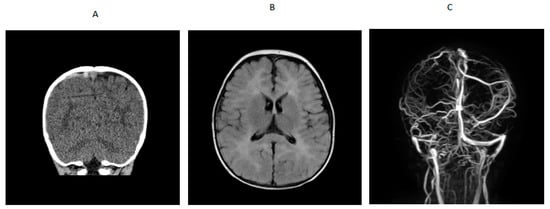

A 7-year-old boy with history of hypertension, familial tall stature and generalized overgrowth was admitted for persistent vomiting, mild leukocytosis of 14,700 and mycoplasma pneumonia. Initial brain MRI was reported as normal. He developed generalized tonic clonic seizures and left hemiparesis on day 3 of hospitalization. Bedside glucose and serum electrolytes were normal. Ammonia was mildly elevated at 58 µmol/L but repeat was less than 9; lipase was 1273 U/L (normal is 23–300 U/L). An emergency head CT scan was read as normal. Neurology was consulted and he was transferred to the pediatric intensive care unit for closer monitoring. A video EEG in the ICU was suggestive of a right > left posterior quadrant cerebral dysfunction. Dilated funduscopic examination showed edema of the optic disc bilaterally without obscuring overlying vessels. Lumbar puncture showed an opening pressure greater than 38 cm of water (normal is less than 25 cm water) with normal cell count. He was started on acetazolamide for pseudotumor cerebri. MRV showed extensive dural venous sinus occlusive disease with extensive superficial and deep collateral veins and review of the previous brain MRI showed a filling defect in the superior sagittal sinus consistent with dural sinus thrombosis (Figure 2) and papilledema. Hypercoagulable work-up showed mildly decreased antithrombin III activity (80%; reference range was 83% to 128%). Factor V Leiden, prothrombin gene mutation, lupus anticoagulant and protein S were normal and protein C activity was low (63% with reference range of 70% to 140%). Metabolic work-up showed plasma homocysteine 71.9 (reference range was 6.6 to 14.8 µmol/L); plasma amino acids showed methionine of 448 µmol/L (reference range was 14 to 50) and free homocystine was 7 (reference range was 0–2 µmol/L). Serum methylmalonic acid was 0.15 (normal is 0.0 to 0.4 µmol/L), serum folate was 14.4 (reference range is 7 to 34.1 ng/mL), serum vitamin B12 was 244 (reference is 213 to 816 pg/mL). Blueprint Genetics Laboratory Homocystinuria Core Panel Plus showed a compound heterozygote pathogenic variant c.325T>C (p.Cys109Arg) and a variant of uncertain significance c1604C>T (p.Thr535Ile) in the CBS gene.

Figure 2. For patient 2. (A) CT scan showing thrombosis of superior sagittal sinus. (B) Brain MRI showed filling defect in superior sagittal sinus. (C) MRV showing dural venous thrombosis with extensive superficial and deep collateral veins.